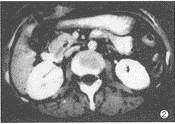

CT表现:(1)胰头轻度增大2例,约3.5cm×3.0cm,胰体、尾部相对缩小;胰钩突饱满、圆隆、分叶9例。 (2)胰头局限性低密度区5例(图1),大小约1.5cm×1.5cm~3.0cm×3.0cm,2例位于胰头前部,向外突起,边界较清楚,3例位于胰头内,边界不清,与胰腺组织呈移行状。2例胰头增大伴有弥漫性密度轻度减低,9例胰钩突密度减低,其中1例密度显著减低,但形态正常。十二指肠降部内侧壁局限性结节3例(图2),大小约1.5cm×2.0cm~2.0cm×2.0cm,密度与软组织相同,边缘清楚。增强扫描胰头病灶呈低密度或不均匀低密度区,十二指肠内侧壁结节有明显强化。 (3)胆总管下端软组织结节、局部管壁增厚、下段管壁均匀增厚各1例(图3),肝内胆管扩张18例,胆总管扩张19例,胆总管下端突然中断16例,逐渐变窄3例,胰管扩张19例。

图1 胰头腺癌。胰头内局限性低密度区,形态不规则,边缘不清楚,伴有胰、胆管扩张 图2 Vater's壶腹绒毛腺瘤恶变。CT表现为胆总管下端结节,突入十二指肠内侧壁 图3 胆总管癌。胆总管壁均匀增厚,有强化,与周围胰头分界不清,与炎症表现相似,手术见肿瘤沿胆总管壁浸润,达肝门,并有肝门淋巴结转移 图4 胰头炎症。胰头弥漫性肿大,内见散在小点状低密度区,其间胰头实质密度均匀,胰头与十二指肠紧密粘连 图5胆总管下端炎症。CT表现为胆总管下端一侧壁局限性增厚,以上胆道有少许积气,病理切片可见纤维组织增生及慢性炎细胞浸润 图6 胰头癌合并炎症。胰头后部(腔静脉左前侧)见边缘模糊小低密度区,于胰颈部有一炎性假囊肿